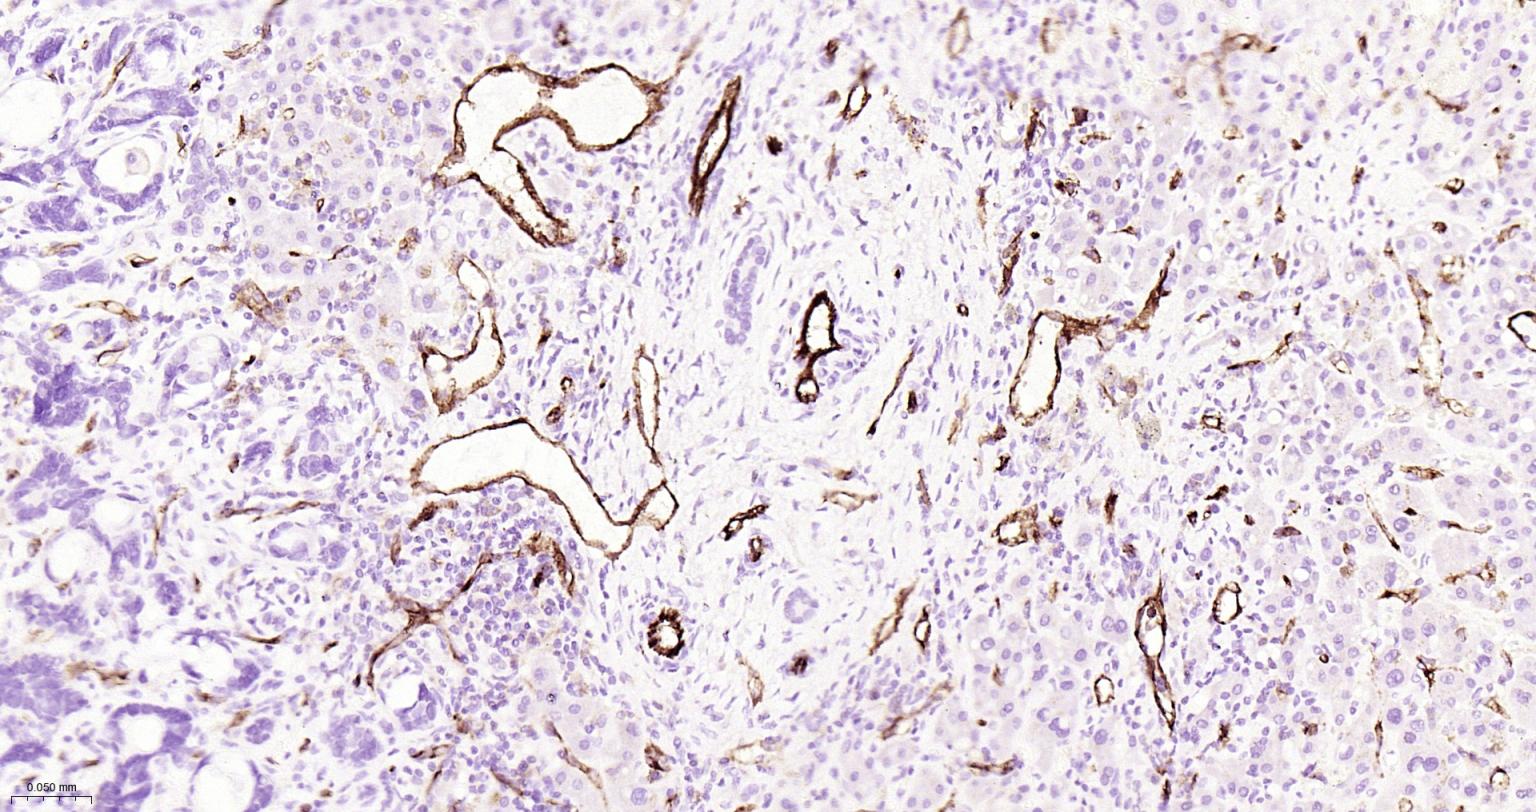

| IHC-P | Human | 1:200-2000 | |

Expressed on platelets and leukocytes and is primarily concentrated at the borders between endothelial cells (PubMed:18388311, PubMed:21464369).

Cell adhesion molecule which is required for leukocyte transendothelial migration (TEM) under most inflammatory conditions (PubMed:19342684, PubMed:17580308).